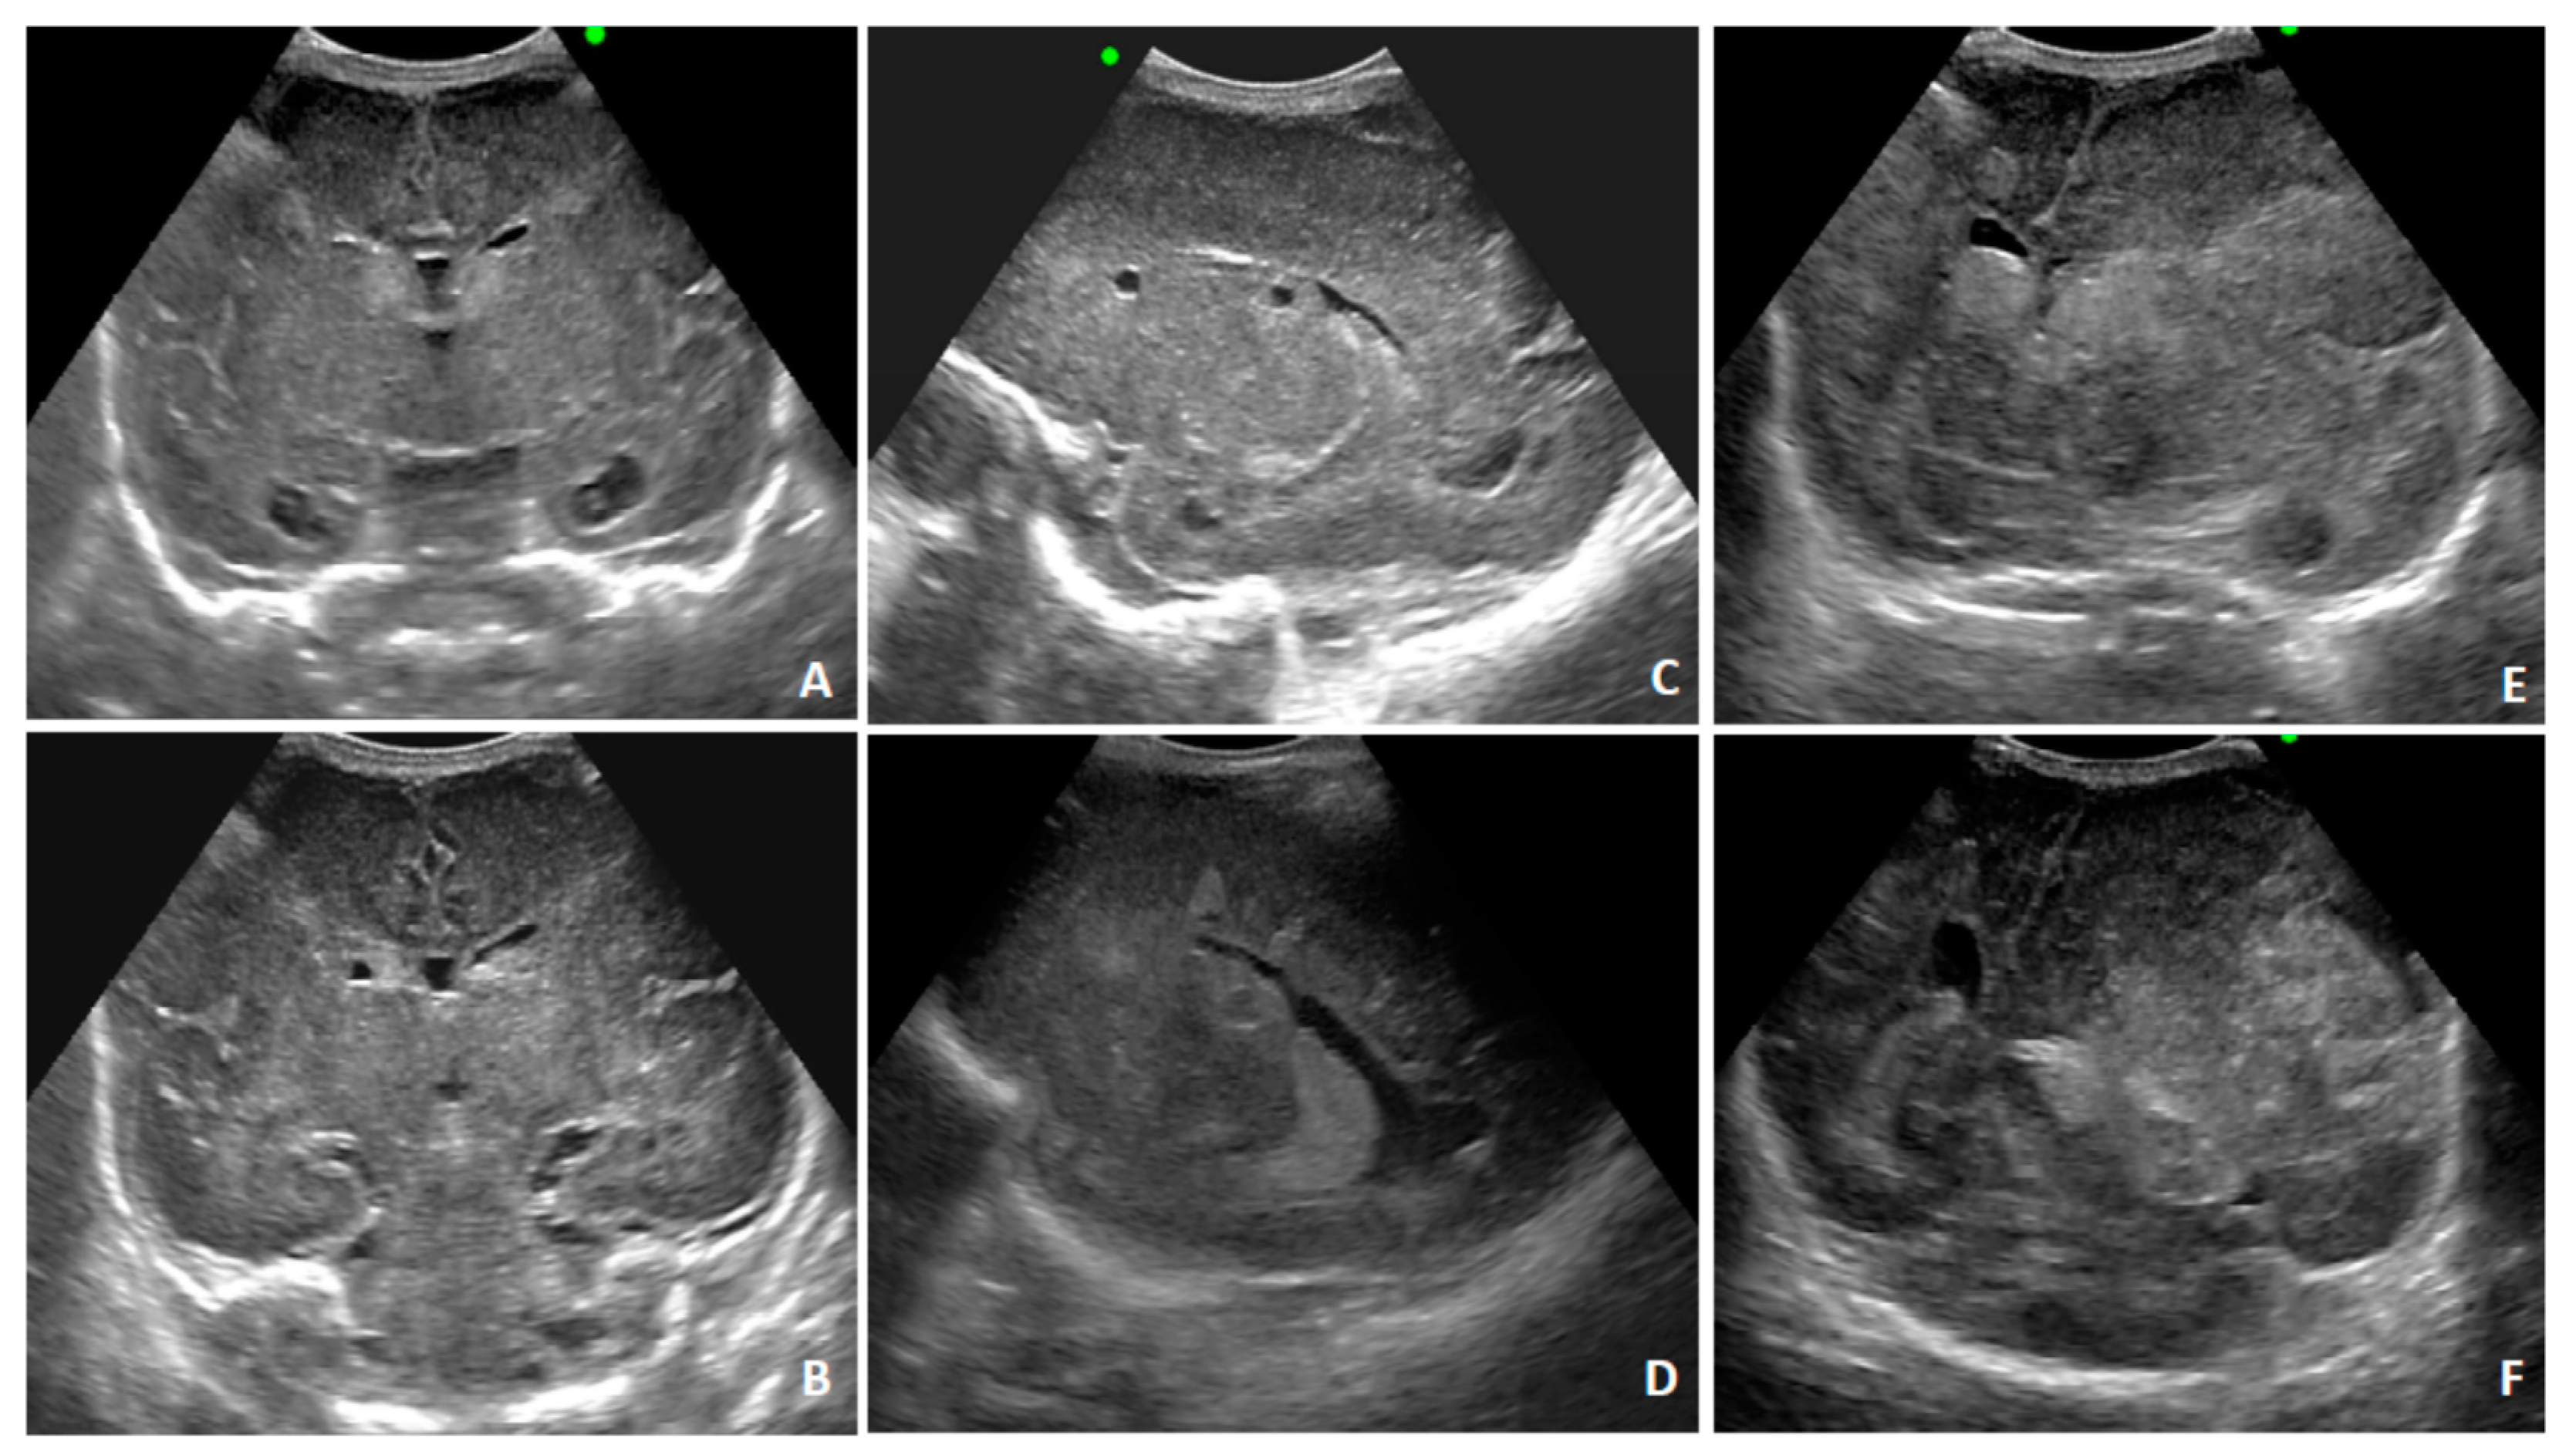

2. Case Presentation